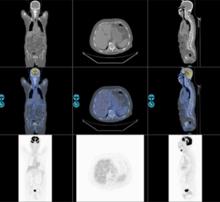

醫學圖像的感興趣區分割研究,是醫學圖像分析中最重要的基礎,準確、魯棒和快速的圖像分割,是定量分析、三維可視化等後續環節之前的最重要步驟,也為圖像引導手術、放療計畫和治療評估等重要臨床套用奠定了最根本的基礎。早期醫學圖像分割研究,主要是直接套用圖像處理的經典方法,如邊界提取和基於灰度的區域增長算法等。後來開始針對不同的解剖位置和成像模態,設計基於成像設備、成像參數和解剖結構等先驗知識的專用圖像分析算法,如利用多參數的MR圖像、決策樹和統計聚類技術來分割腦組織的白質和灰質。隨著圖像分析和計算機視覺理論方法的不斷豐富,醫學圖像感興趣區分割也出現了很多新突破。參數動態輪廓線模型,(active contour model)開創性地提出了高層模型指導、底層圖像特徵驅動的圖像分割思想,通過最小化模型的內外部能量得到分割結果,在隨後20多年中得到研究者的廣泛關注和不斷發展 。動態表現模型(active appearance model) ,動態形狀模型(active shape model) 都是這一類的代表方法。Osher和Sethian提出的水平集(1evel set)方法 ,利用數值方法模擬各種曲面演化,後來作為一種數值模擬和分析的方法,被廣泛運用於曲線或曲面的運動跟蹤,在醫學圖像分割中也得到廣泛套用。但目前大多數分割算法對醫學圖像成像參數和曲線、曲面的初始位置較敏感,沒有人工參與,難以做到魯棒分割不同設備乃至同種設備、不同參數的醫學圖像。

醫學圖像分析圖1. 醫學圖像分割